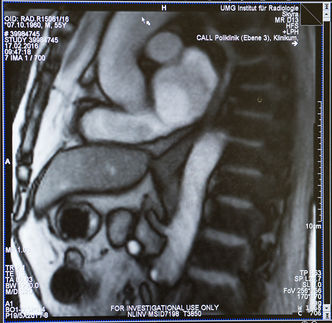

Bild: Universitätsklinikum Würzburg, Quelle: Prof. Hiroharu Inoue